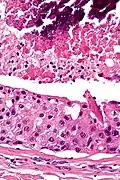

| Low magnification micrograph of a salivary duct carcinoma with characteristic comedonecrosis (left of image) adjacent to normal parotid gland (right of image). H&E stain. | |

Their histologic appearance is similar to ductal breast carcinoma.

Very low mag. -